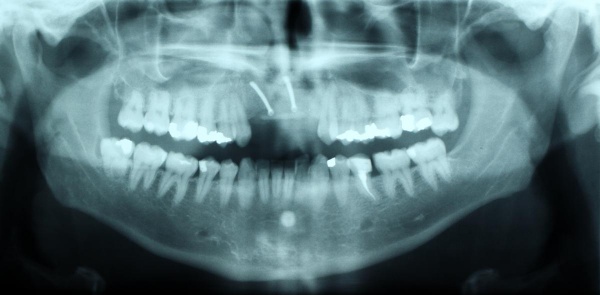

Ein 31jähriger Patient stellte sich am 10.11.2011 in der Implantatsprechstunde vor mit der Bitte um Befürwortung einer implantatgetragenen prothetischen Lösung für eine seit 1997(!) bestehende Schaltlücke 12 bis 22 nach tätlicher Auseinandersetzung.

Die Lücke war bis dato über eine insuffiziente Teilprothese versorgt. Es bestand eine ausgeprägte Oberkieferatrophie in allen Dimensionen mit negativer Stufe im Verhältnis Oberkiefer zu Unterkiefer (Bild) sowie Elongation der Unterkieferfrontzähne (Abb. 9).

Zur Wiederherstellung von Phonetik und Ästhetik und Verhinderung einer weiteren Elongation der Unterkieferzähne wurden für die Rekonstruktion der Oberkieferfront 4 Einzelzahnimplantate beantragt nach vorheriger Augmentation von Beckenkamm.

Zum Ausgleich der konsekutiv vorliegenden Weichgewebsatrophie erfolgte im Juni 2012 nach Genehmigung des Antrags durch das Sanitätsamt der Bundeswehr zunächst die Implantation von 2 Weichgewebsexpandern (Firma Osmed) im Oberkiefer (Abb. 10). Nach Schaffung eines adäquaten Weichgewebsbettes wurde im Juli 2012 zur Korrektur der extremen Hartgewebsatrophie eine Augmentation vom Beckenkamm durchgeführt (Abb. 11). Im Dezember 2012 erfolgten in Lokalanästhesie nach ungestörter Einheilung die Materialentfernung der Osteosyntheseschrauben und die Implantation von 4 dentalen Implantaten (Firma Nobel Biocare, Replace straight, Abb. 12). Durch Atrophie und die rekonstruktiven Operationen bedingt, wurde zur Korrektur der ungenügenden Weichgewebsverhältnisse eine Vestibulumplastik nach 3 Monaten mit Einlagerung einer bioresorbierbaren Membran (Firma Botiss, Mucoderm) durchgeführt. Nach weiteren 3 Monaten erfolgte die Freilegung der Implantate (Abb. 13) mit einer Rolllappenplastik an jedem Implantat zur vestibulären Rekonturierung der Schleimhaut.